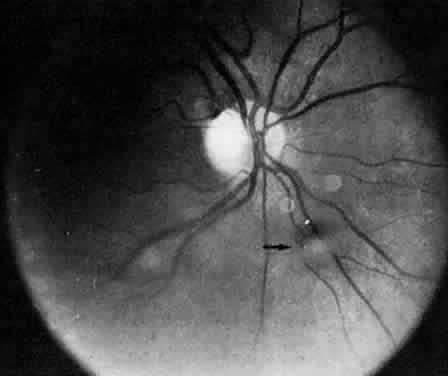

The diagnosis of pars planitis is based completely on history and clinical findings. Pars planitis is a chronic uveitis in which the most severely inflamed part of the eye is the vitreous. The vitreous should show the greatest concentration of inflammatory cells. Pars planitis is also characterized by the presence of vitreous fluff balls (Fig. 8) or a snowbank in the inferior vitreous base. Macular edema is another important feature in pars planitis, because pars planitis is one of the most common causes of cystoid macular edema in young adults. Pars planitis is a disease of the young and early middle-aged adults. The onset of pars planitis is usually in the late teens and early twenties; it rarely occurs after age 30.

Fig. 8. Posterior pole in a patient with intermediate uveitis. The arrow indicates a vitreous opacity resembling a puffball.